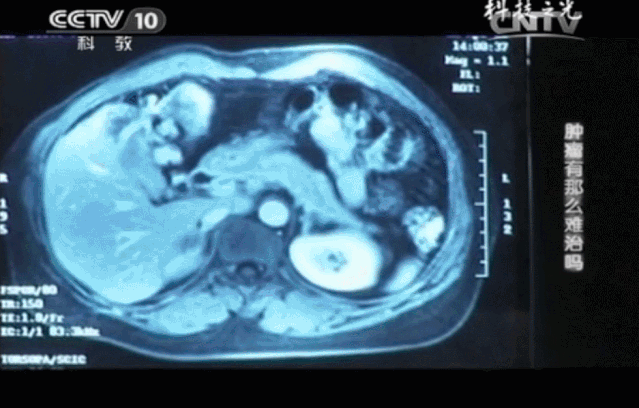

CCTV-10曾报道了一例免疫细胞疗法治疗癌症晚期患者的真实案例——《肿瘤有那么难治吗》:49岁的王女士不幸患上了癌症,诊断为晚期,失去手术机会,化疗难以耐受,生命似乎走到了尽头。后来在自己的努力坚持和医生的帮助下,她接受了一个特殊的治疗方式——细胞免疫治疗,并最终重获新生。

王女士的肝脏上毫无征兆地出现了一个直径约为8cm的肝转移肿瘤,肿瘤引发的巨大疼痛不间断地折磨着王女士,继续化疗只会加重她的身体负担,遏制肿瘤的效果也并不尽如人意。

不仅如此,连续4个月的CT结果对比分析,肝转移瘤从8公分缩小到2.5公分,肿瘤标记物指标回归正常,这些都说明肿瘤正在被免疫细胞一点点消灭。王女士终于回归了正常的生活。